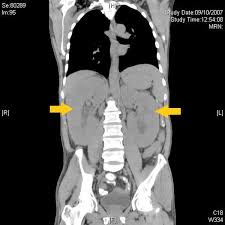

Angioimmunoblastic T-Cell Lymphoma / Amazon Com Reversing Angioimmunoblastic T Cell Lymphoma As God Intended The Raw Vegan Plant Based Detoxification Regeneration Workbook For Healing Patients Volume 1 9781395183608 Central Health Books : This lymphoma generally develops in the small intestine or colon.. Clinical and laboratory features at diagnosis in 77 patients. It is a systemic disease that presents with generalized lymphadenopathy, hepatosplenomegaly, constitutional symptoms, skin rash, anemia. It is one of the. Are you sure your patient has angioimmunoblastic t cell lymphoma? Angioimmunoblastic t cell lymphoma (aitl) is a peripheral t cell lymphoma characterized by systemic disease, a polymorphous infiltrate involving lymph nodes, and a prominent proliferation of high endothelial venules and follicular dendritic cells (who 2008).

Angioimmunoblastic t cell lymphoma (aitl) presents in older patients and the median age at diagnosis is approximately 60. Anubha bajaj* ab diagnostics, new delhi, india. Dr flora poon, victorian dermatology registrar, st. These include skin rashes, joint pain, and some. Angioimmunoblastic t cell lymphoma (aitl) is a peripheral t cell lymphoma characterized by systemic disease, a polymorphous infiltrate involving lymph nodes, and a prominent proliferation of high endothelial venules and follicular dendritic cells (who 2008).